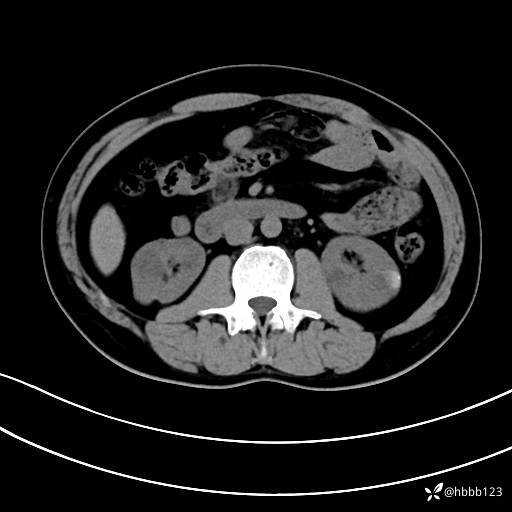

静脉期: